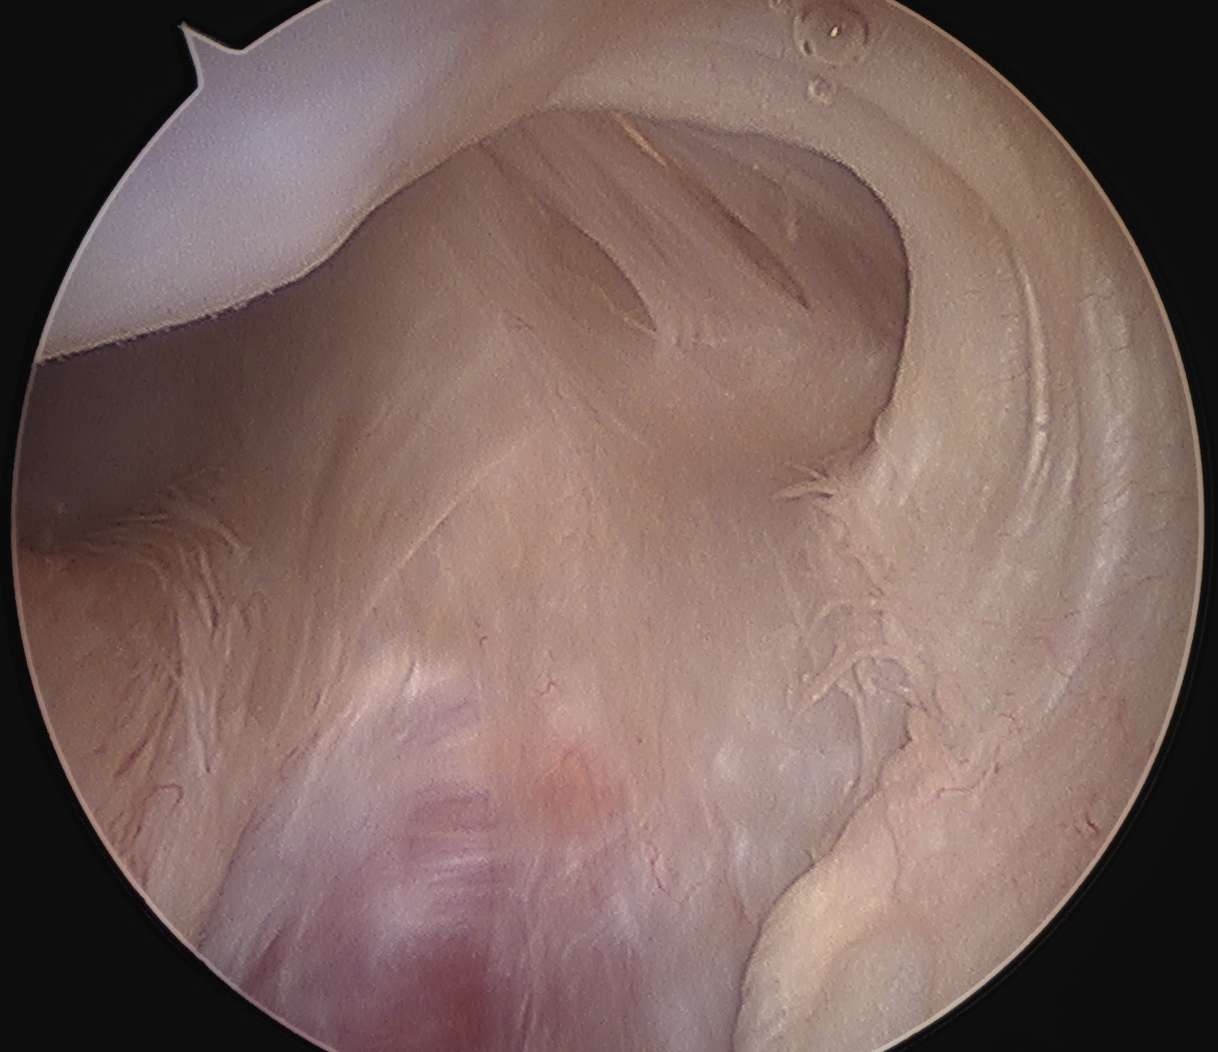

Arthroscopy

Anterior labral tears

Hill Sachs lesion

Anterior glenoid bony deficiency - inverted pear appearance